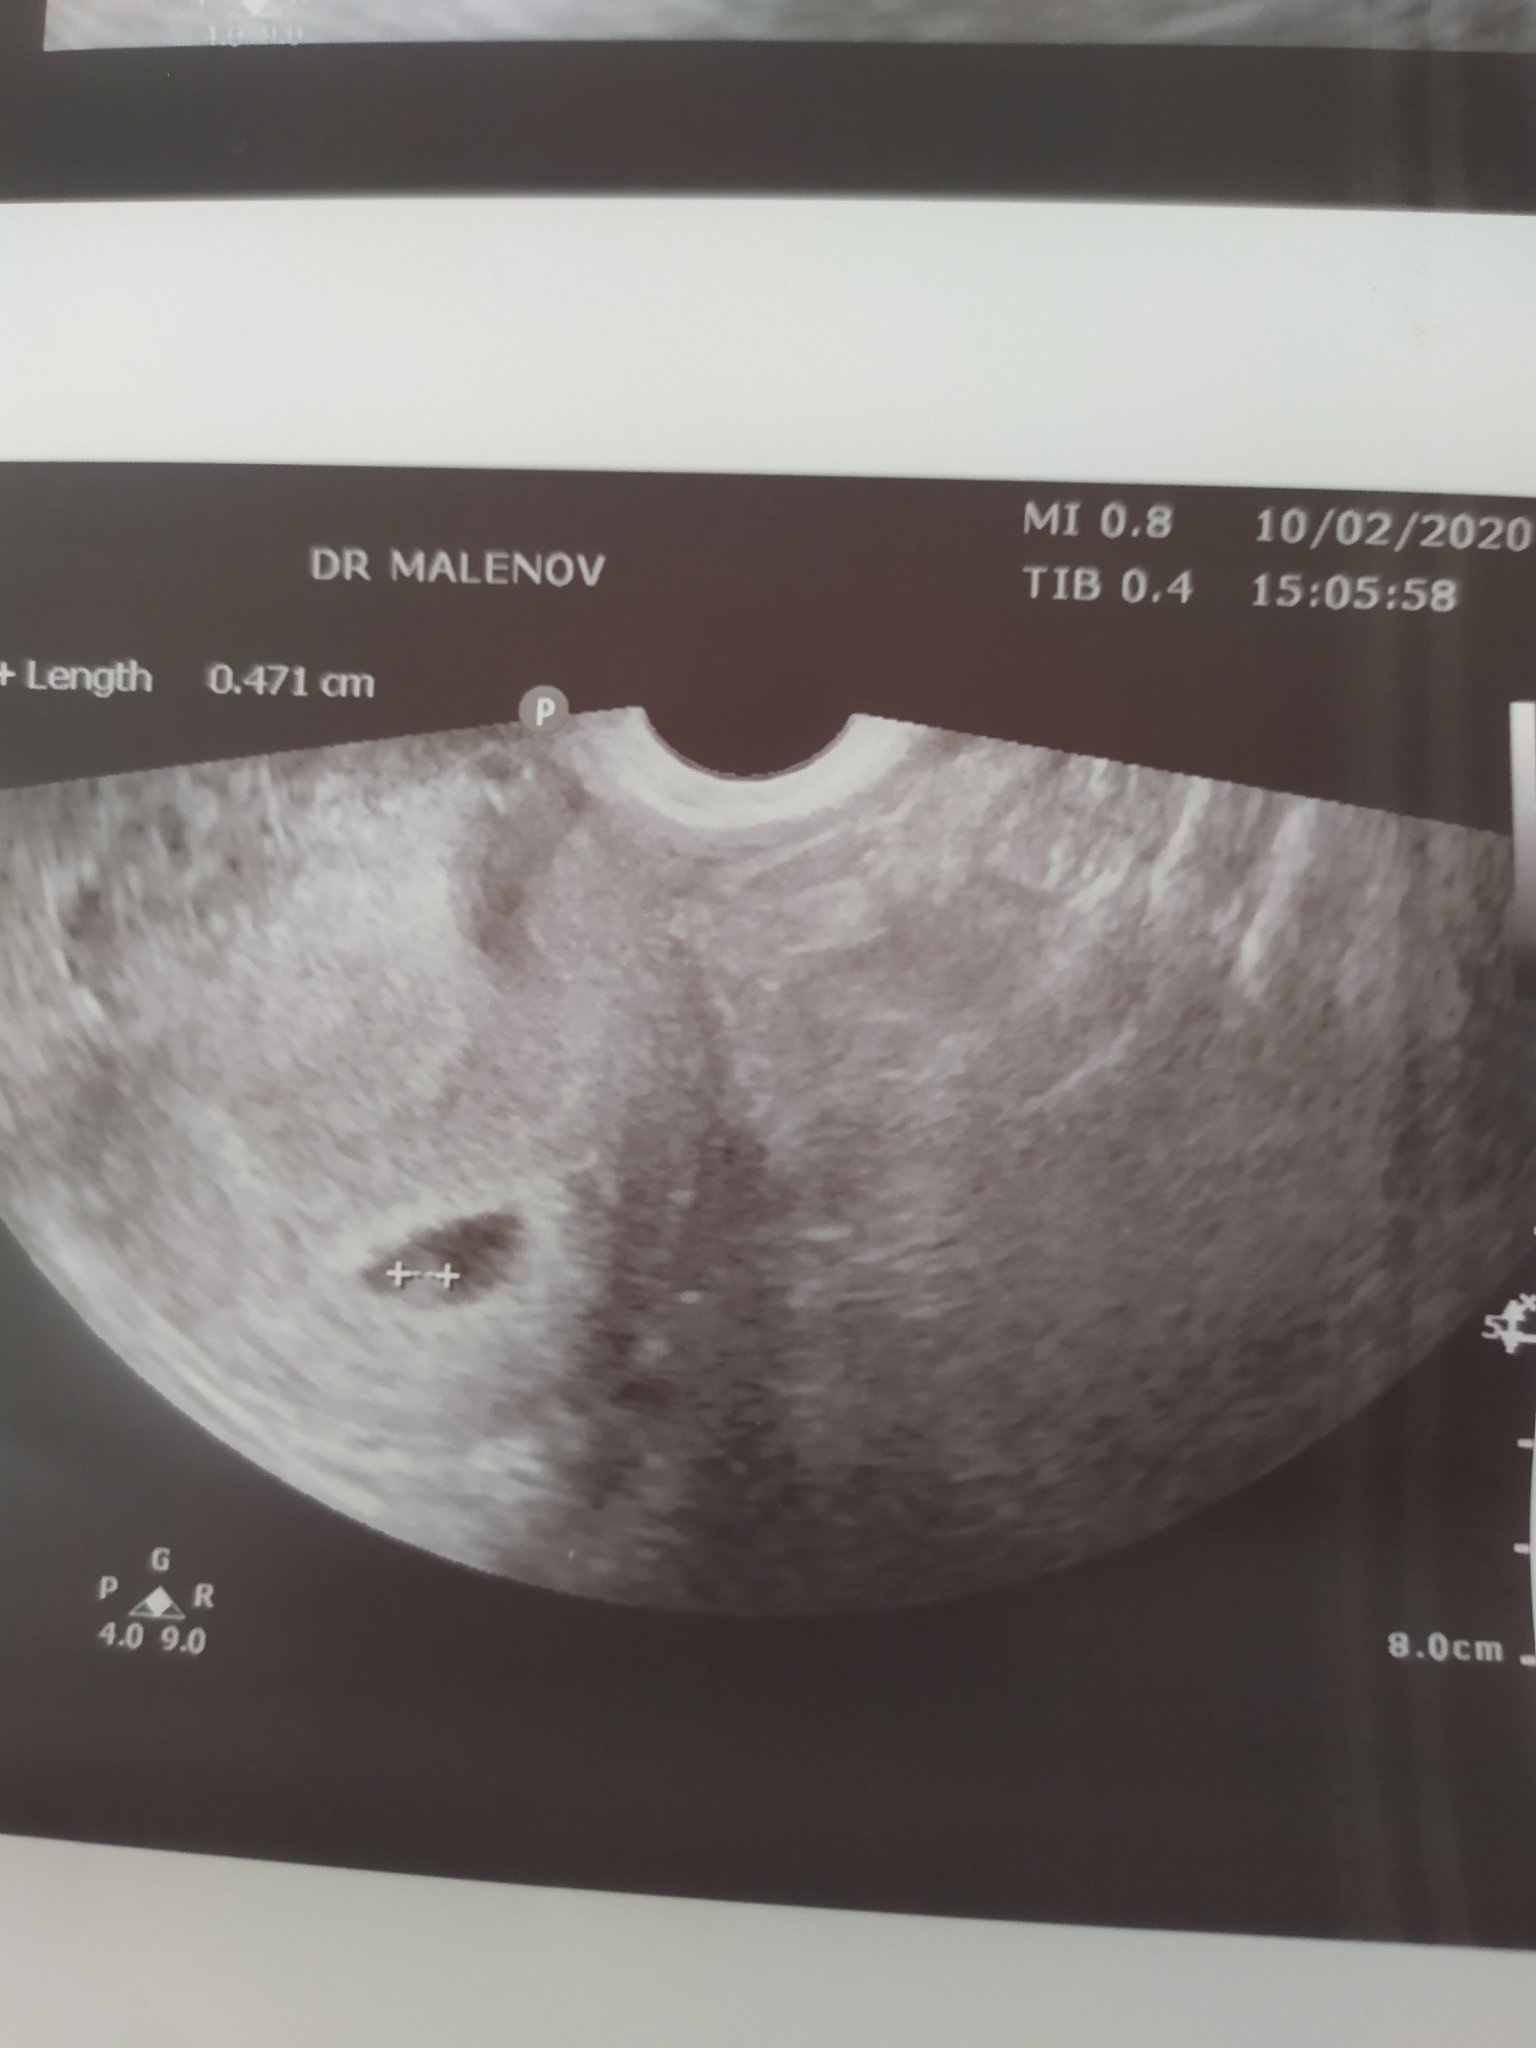

Бях на преглед, чухме сърчице

след всички премеждия и изпитания, които минахме това беше най-прекрасният звук!

в 6 г.с. съм, според календара термина ми е на 03/10.